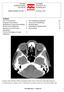

8. Hvad er den mest sandsynlige diagnose?